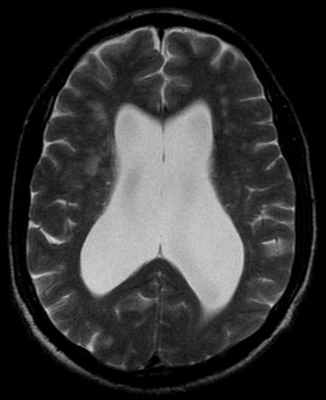

При МРТ головного мозга выявляют расширение III и боковых желудочков. Особенно значительно расширены III желудочек, височные и фронтальные рога боковых желудочков. Гидроцефалия при этом синдроме является сообщающейся, так как сильвиев водопровод проходим.

- Вентрикуломегалия

- Баллонообразное расширение передних рогов боковых желудочков до 30% и более от диаметра черепа. При данной патологии особенно значительно расширены III желудочек, височные и фронтальные рога боковых желудочков, что приводит к появлению характерной формы желудочковой системы в виде “бабочки” на аксиальных срезах.

МРТ головы пациента с НТГ: обращает на себя внимание выраженная вентрикуломегалия

при отсутствии значимой атрофии вещества головного мозга